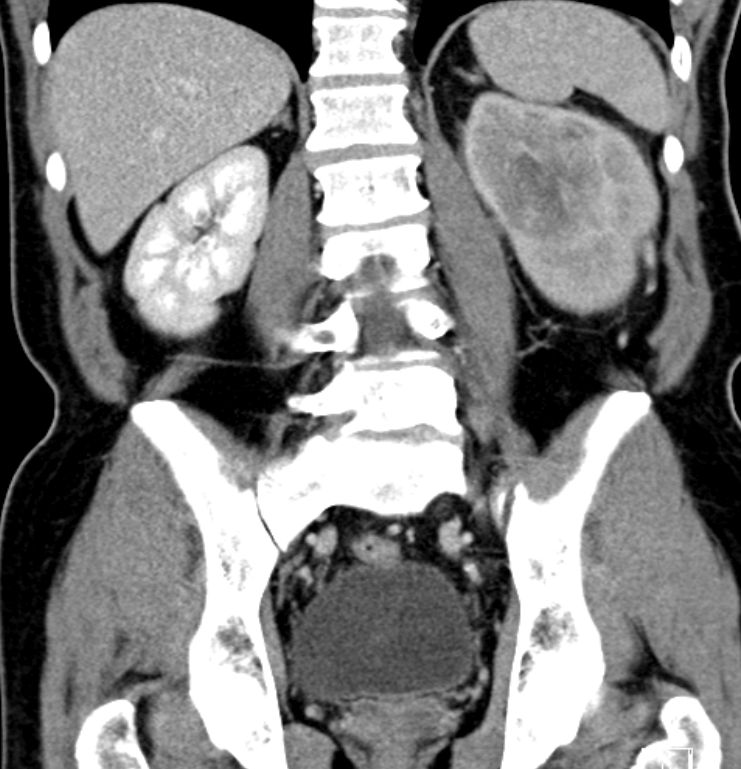

| CT | 81-jährige Frau mit einem großen, die linke Niere einnehmendem

Tumor. Histologie: Urothelkarzinom.![]() | |||

Die linke Nierenarterie ist von LK-Metastasen eingeschlossen.![]() | ||||

Auch im Mediastinum große LK-Metastasen.![]() | ||||